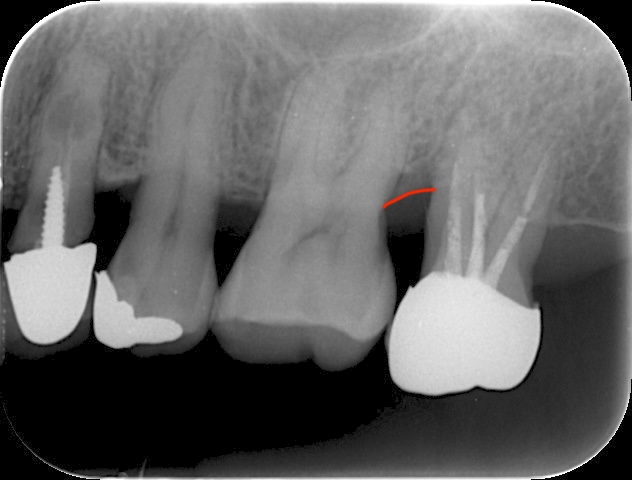

診査・診断:歯周病で支持骨の喪失が大きく、動揺・ポケット深化を認める。精査の上、エムドゲインによる再生療法で保存の可能性ありと診断。

手術の流れ:局所麻酔下で剥離・デブライドメント、歯根面処理→エムドゲイン塗布、必要に応じ人工骨併用、縫合。手術時間はおよそ1.5時間。

経過:術後の腫脹・疼痛は軽度で、2週間前後で抜糸。数か月後、骨様組織の充填とポケット改善を確認。現在はメインテナンスを継続しながら安定を維持。